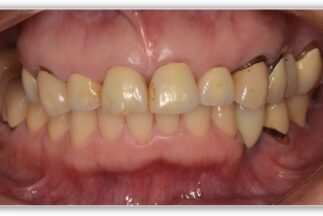

- Before

【症例ステータス】

| 年齢 | 性別 | 治療期間 | 治療費概算 |

|---|---|---|---|

| 57歳 | 女性 | 2年 |

480万 ※費用は範囲によって異なります。 |

| 主訴 | |

|---|---|

| 治療内容 | 上顎右側サイナスリフト インプラント埋入上顎3本 下顎3本 上部構造モノリシックジルコニアクラウン修復 |

| リスクについて | インプラント周囲炎 スクリューの緩みなど |